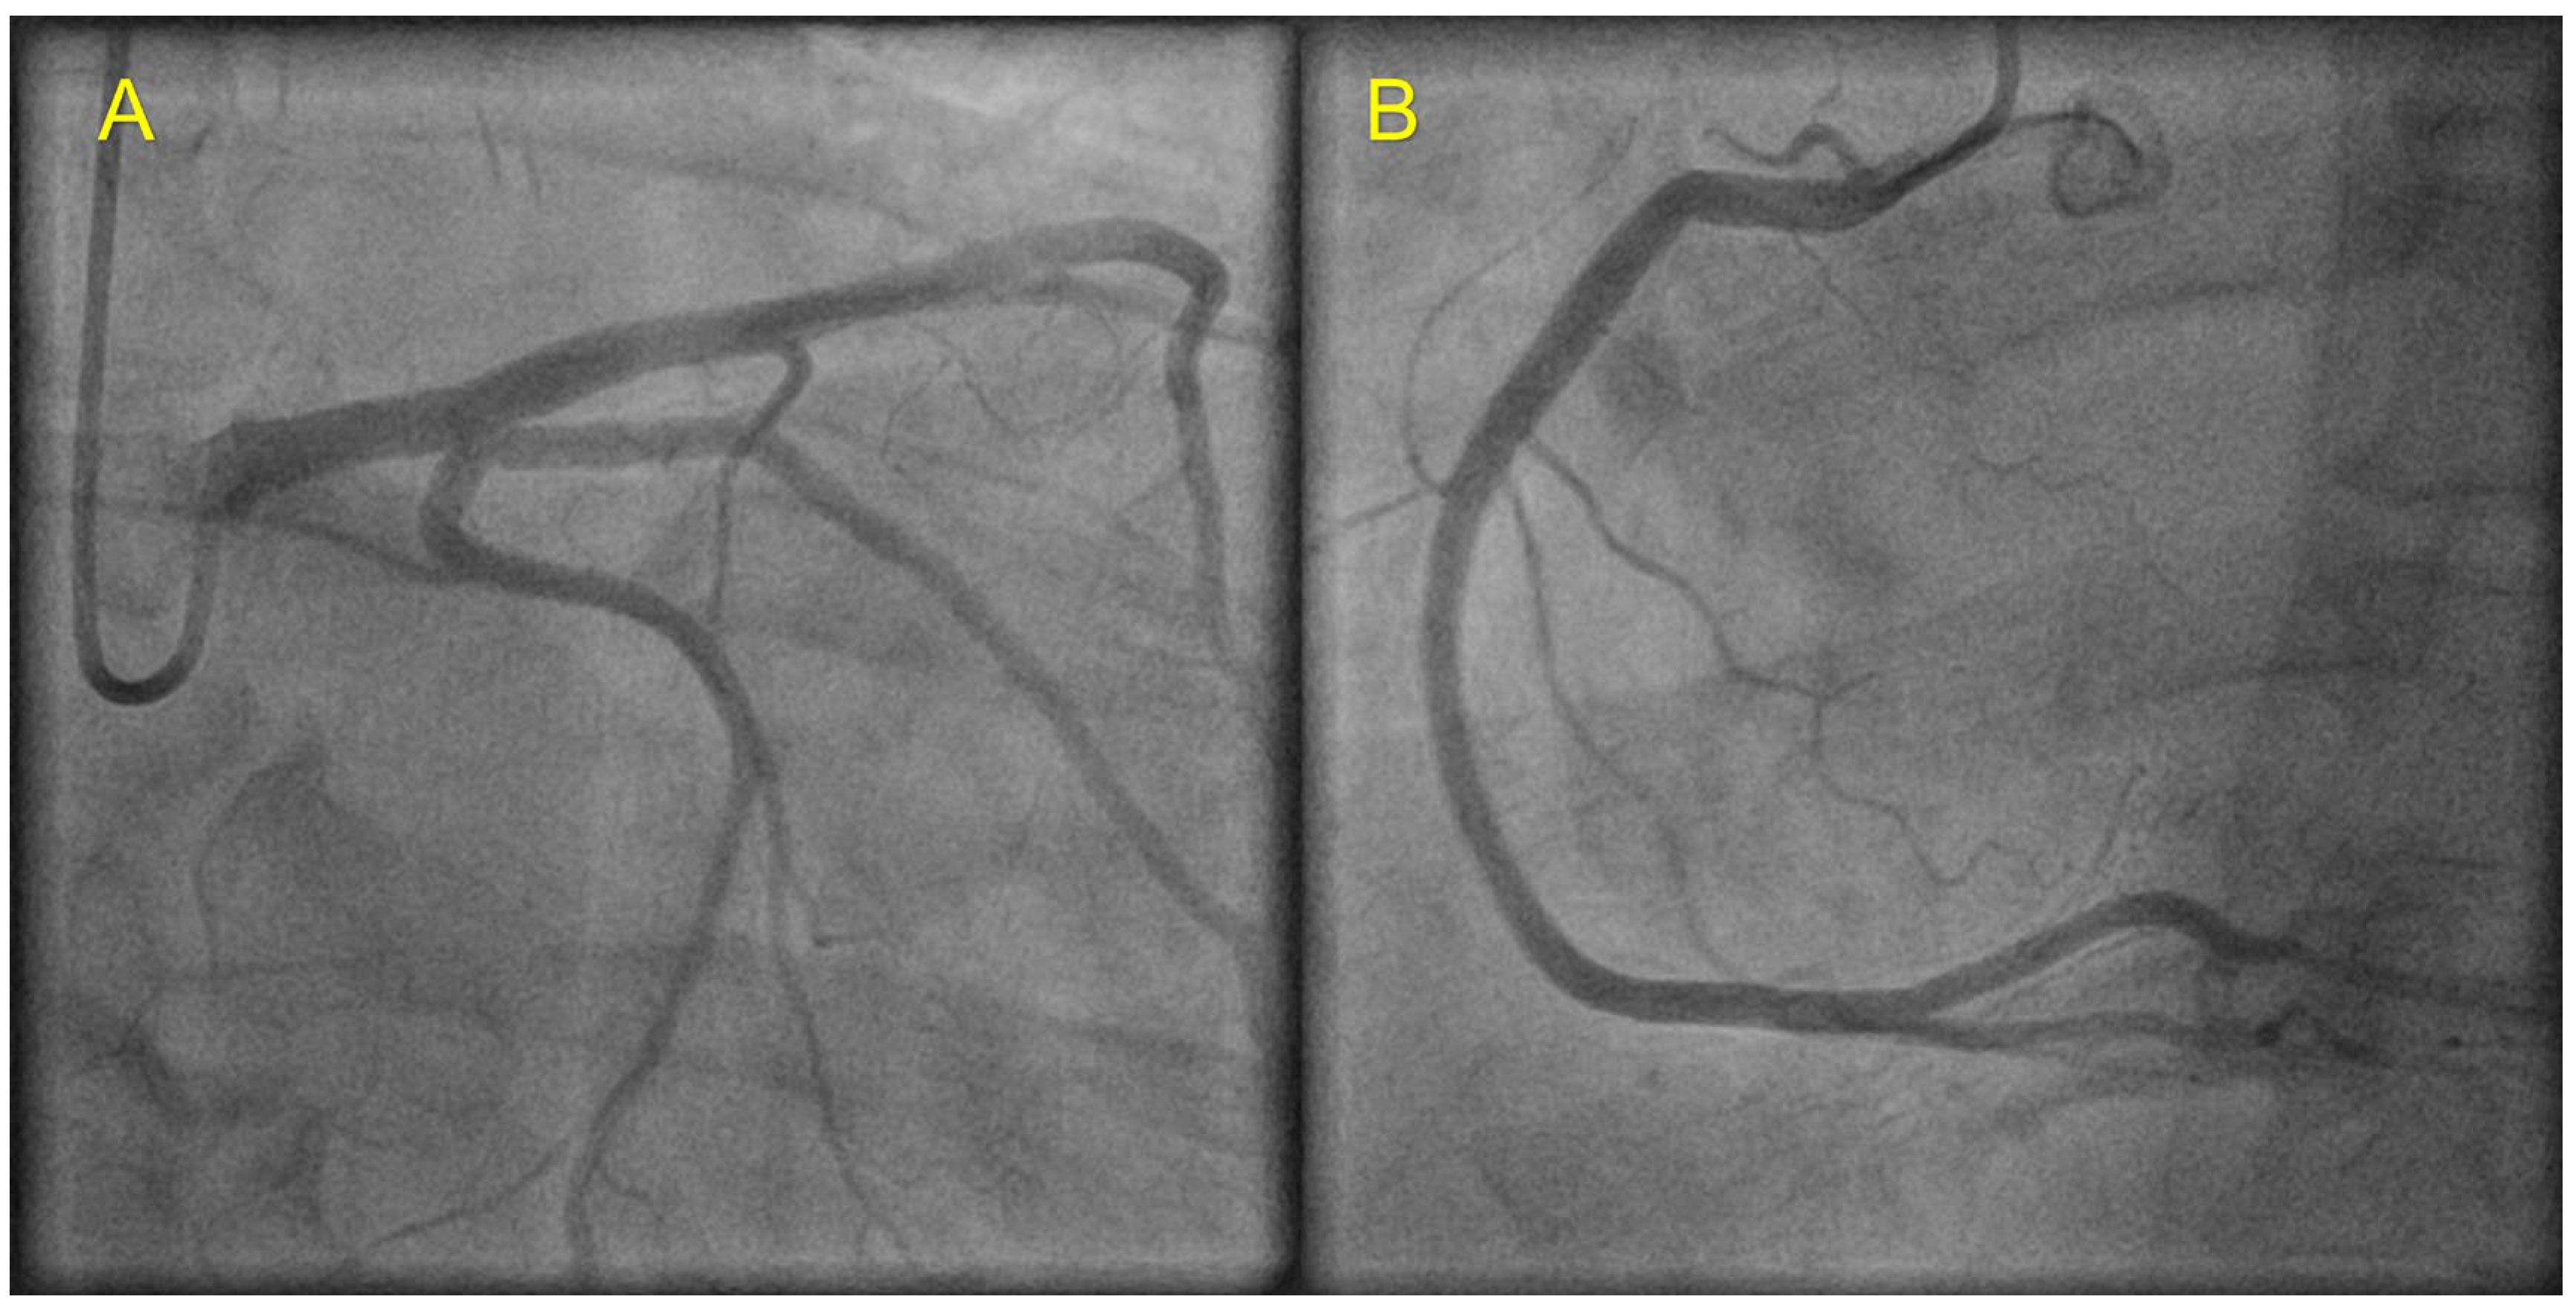

| Echocardiography | Hypokinetic non-dilated cardiomyopathy LVEF = 42% Mild mitral regurgitation IAS aneurysm | Hypokinetic non-dilated cardiomyopathy LVEF = 34% Mild mitral regurgitation IAS aneurysm | Left ventricular concentric hypertrophy LVEF = 54% |

| Cardiac magnetic resonance imaging | Hypokinetic non-dilated cardiomyopathy Left ventricular non-compaction LVEF = 50% | Hypokinetic non-dilated cardiomyopathy Regional sub-epicardial fibrosis LVEF = 41% | Not carried out |

| Coronary angiography | Normal | Normal | Not carried out |